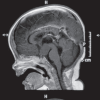

Polydactyly is a relatively common abnormality in infants. However, it can be a marker of a wide variety of neurological and systemic abnormality. Hence, it is important for pediatrician and physician to have insight into the various association of this apparently innocuous anomaly. In this write-up, we report an extremely rare syndrome associated with polydactyly that is Pallister-Hall syndrome. A 10-month-old male child born by lower segment cesarean section presented with global delay associated with microcephaly, frontal bossing, hypertelorism, flat nose, short philtrum, incomplete cleft in the upper lip and hard palate, polydactyly, and syndactyly. The child presented with repeated vomiting and crying episodes. The patient was investigated which revealed a hypothalamic hamartomas. Pallister-Hall syndrome is a very rare autosomal dominant genetic disorder due to mutation in GLI3 gene in the short arm of chromosome 7 with variable penetrance and expressivity.